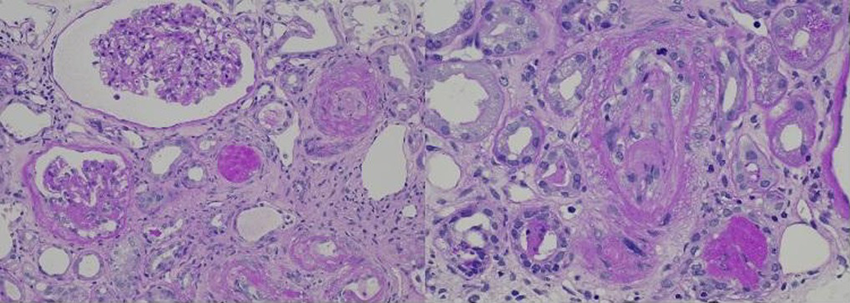

腎生検の拡大像(左:PAS染色×200,右×400)を示す。血管病変の所見として正しいのはどれか。

次にこの症例の血管病変の特徴を拡大して観察する。まず、病変の主座は小葉間動脈の末梢から輸入細動脈にかけての細小動脈レベルである。内膜が肥厚して内腔が閉塞していることが分かる。左の写真のように内膜の肥厚が浮腫性で粘液様に見える場合、mucoid intimal thickeningと表現され、強皮症の腎クリーゼの時にしばしば出現する。右の写真のように細動脈の内膜に炎症細胞浸潤とフィブリン血栓が観察されると、抗リン脂質抗体症候群の内膜病変(TMA)の可能性も出てくる。悪性高血圧もこのレベルの血管に内膜傷害をきたし、しばしば中膜や外膜に波及するフィブリノイド壊死を来す。この症例では中膜は保たれ、フィブリノイド壊死とは言えない。オニオンスキン様の内膜肥厚は高血圧性動脈硬化症でよく見られる所見で、もう少し中枢の小葉間動脈や弓状動脈が好発部位である。弾性線維染色を行うと弾性線維と膠原線維の多層化で確認される。この症例では中枢レベルの血管は含まれておらず、またオニオンスキン様の変化も確認できない。